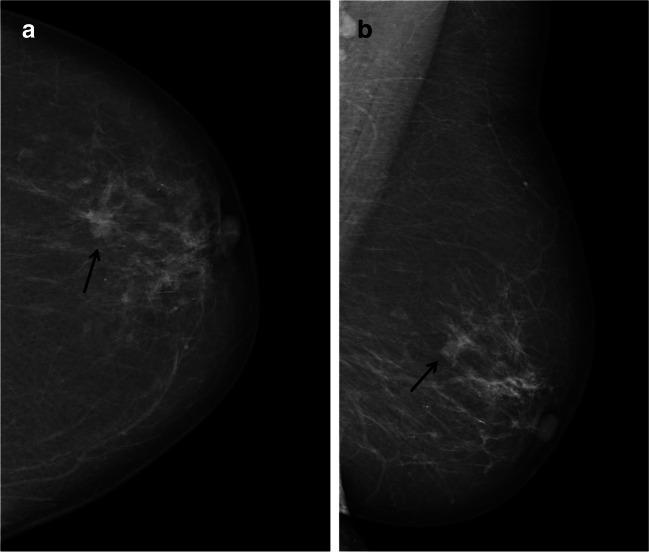

Data were extracted from the Cancer Registry of Norway for 487,118 women who participated in BreastScreen Norway, 2006-2017, with 2 years of follow-up. All mammograms were independently interpreted by two radiologists, using a score from 1 (negative) to 5 (high suspicion of cancer). A score of 2+ by one of the two radiologists was defined as discordant and 2+ by both radiologists as concordant positive. Consensus was performed on all discordant and concordant positive, with decisions of recall for further assessment or dismiss. OR was estimated with logistic regression with 95% confidence interval (CI), and histopathological tumor characteristics were analyzed for screen-detected and interval cancer.

Among screen-detected cancers, 23.0% (697/3024) had discordant scores, while 12.8% (117/911) of the interval cancers were dismissed at index screening. Adjusted OR was 2.4 (95% CI: 1.9-2.9) for interval cancer and 2.8 (95% CI: 2.5-3.2) for subsequent screen-detected cancer for women dismissed at consensus compared to women with concordant negative scores. We found 3.4% (4/117) of the interval cancers diagnosed after being dismissed to be DCIS, compared to 20.3% (12/59) of those with false-positive result after index screening.

Twenty-three percent of the screen-detected cancers was scored negative by one of the two radiologists. A higher odds of interval and subsequent screen-detected cancer was observed among women dismissed at consensus compared to concordant negative scores. Our findings indicate a benefit of personalized follow-up.

• In this study of 487,118 women participating in a screening program using independent double reading with consensus, 23% screen-detected cancers were detected by only one of the two radiologists. • The adjusted odds ratio for interval cancer was 2.4 (95% confidence interval: 1.9, 2.9) for cases dismissed at consensus using concordant negative interpretations as the reference. • Interval cancers diagnosed after being dismissed at consensus or after concordant negative scores had clinically less favorable prognostic tumor characteristics compared to those diagnosed after false-positive results.